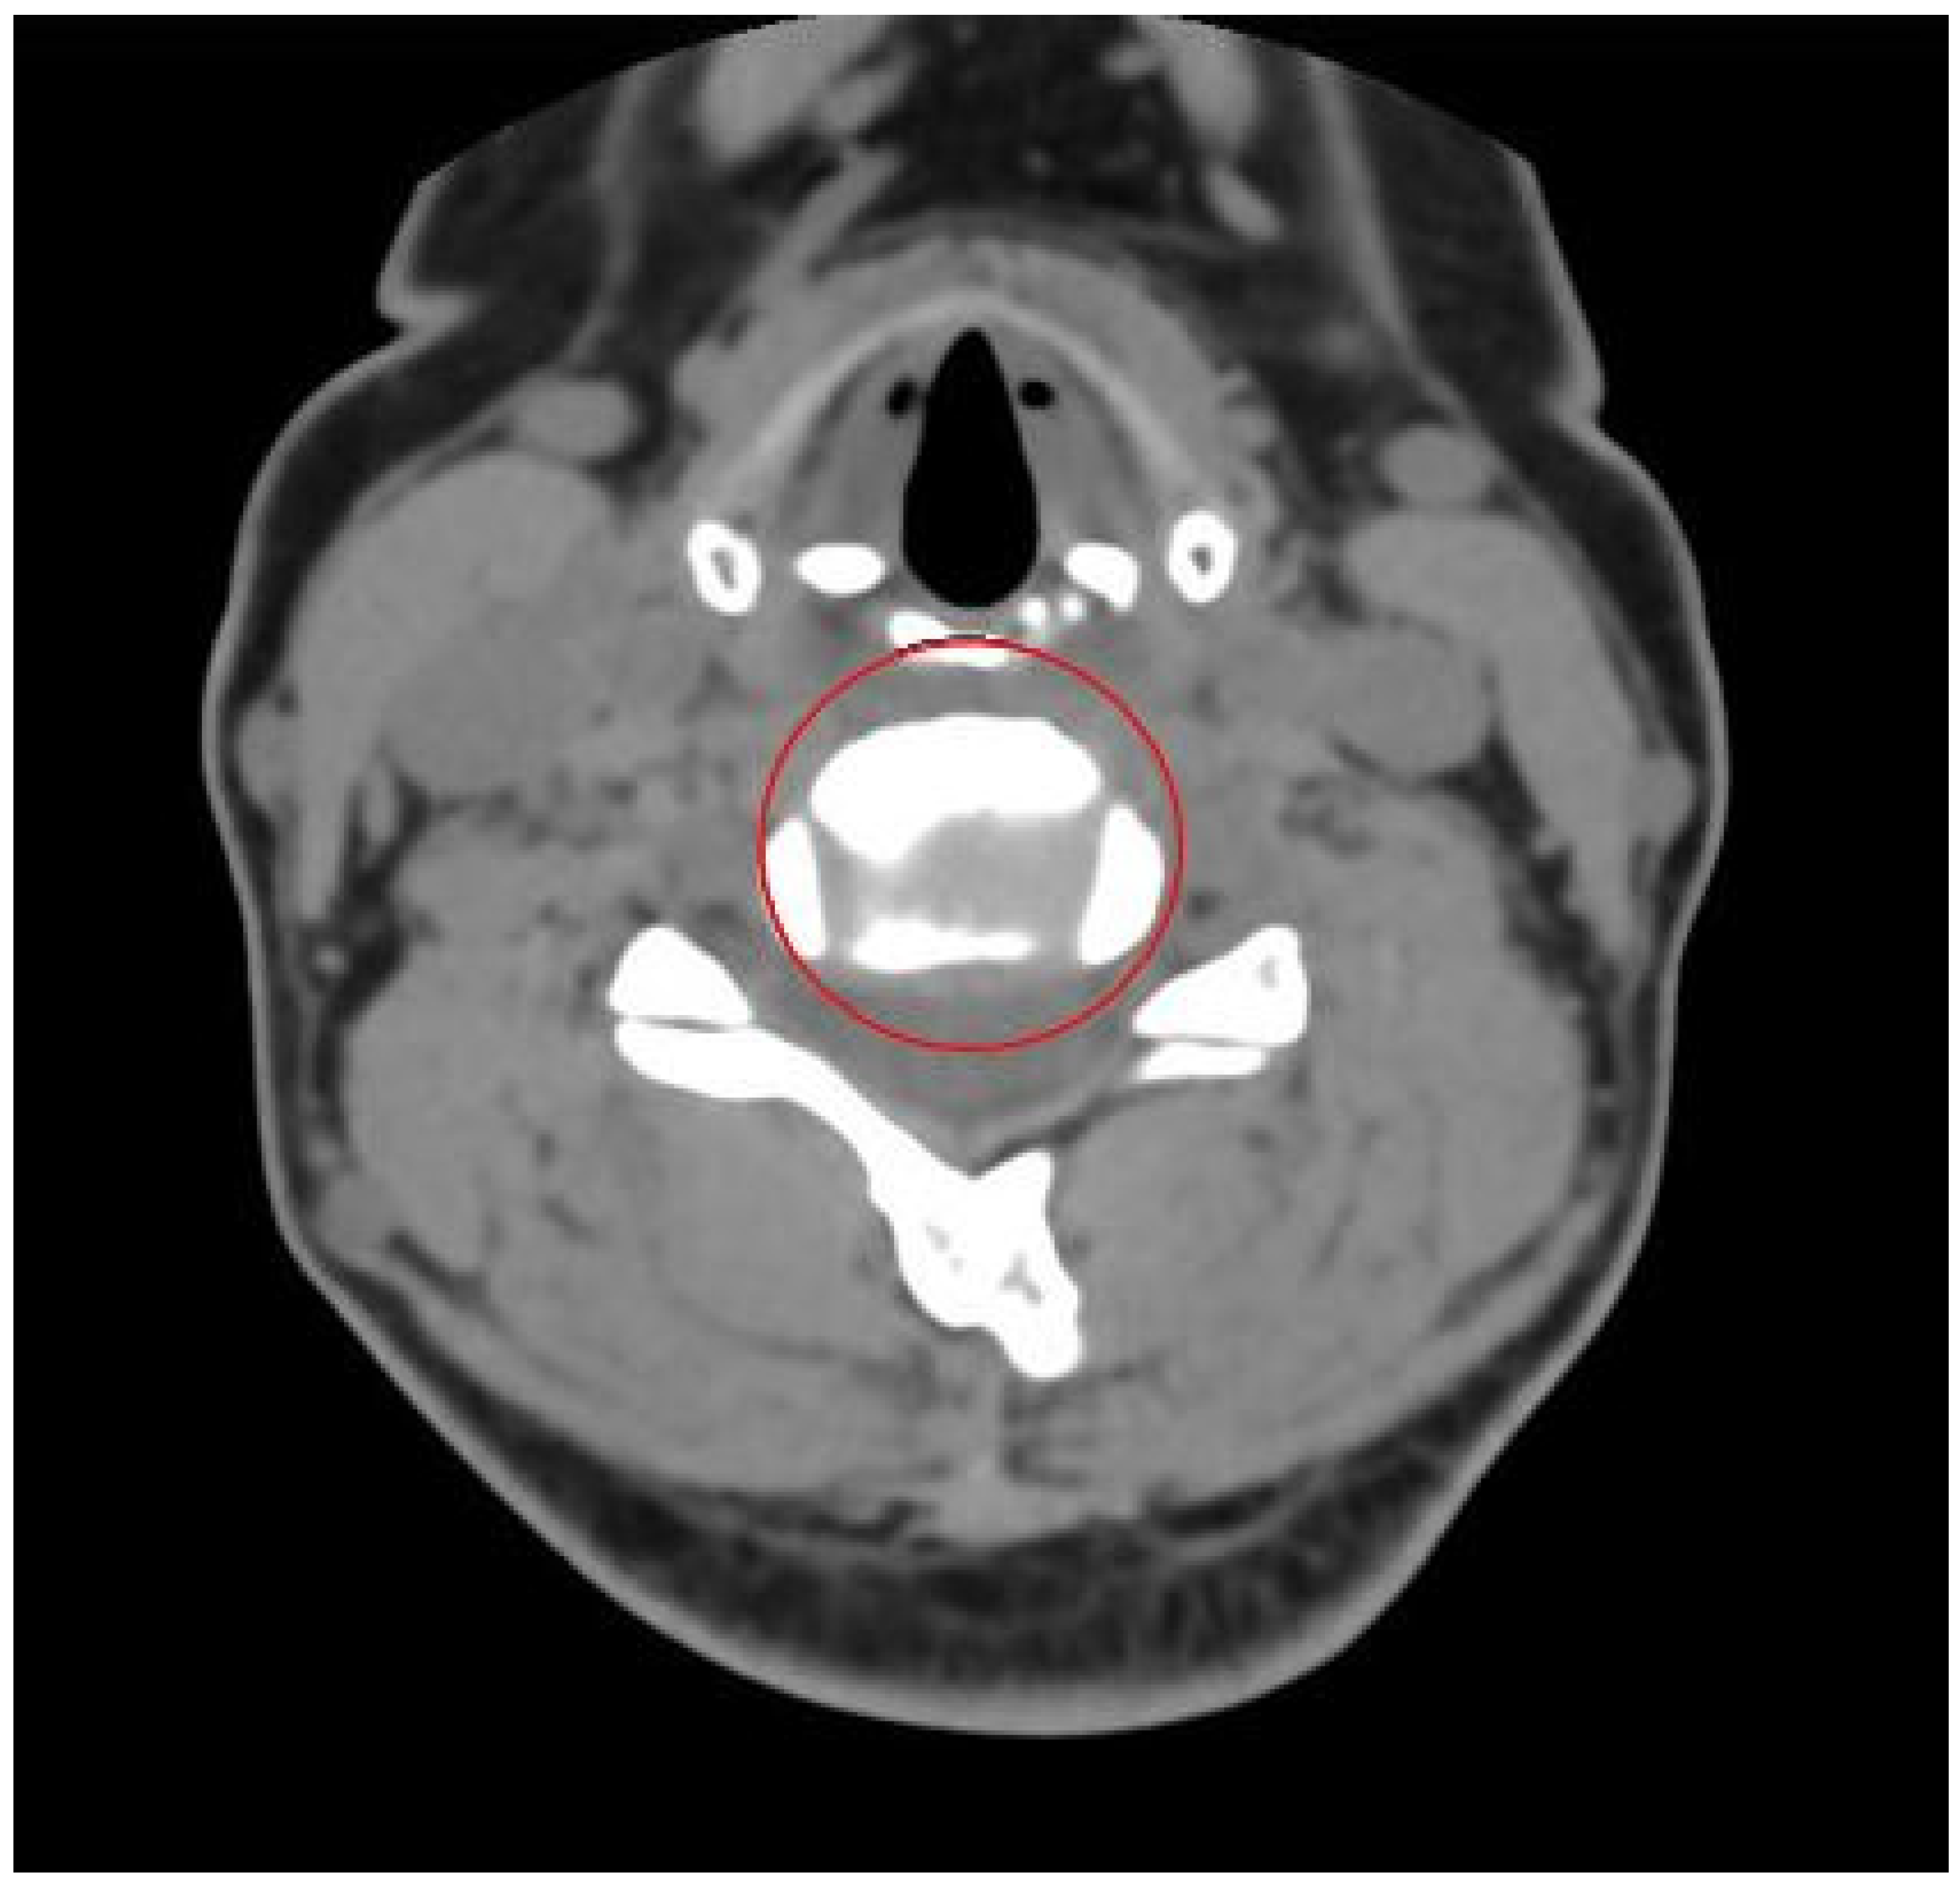

- Datasets specifically aimed at cervical intervertebral disc segmentation are developed. The proposed datasets incorporate inter-layer interpolation to address the inconsistency in longitudinal and transverse pixel spacing in CT sequence images. By selecting frames with prominent intervertebral disc regions through data significance selection and then constructing data groups where three consecutive layer images correspond to one label via manual annotation, the datasets provide important support for research in cervical disc segmentation.

3.5. Construction of Cervical Intervertebral Discs Segmentation Datasets